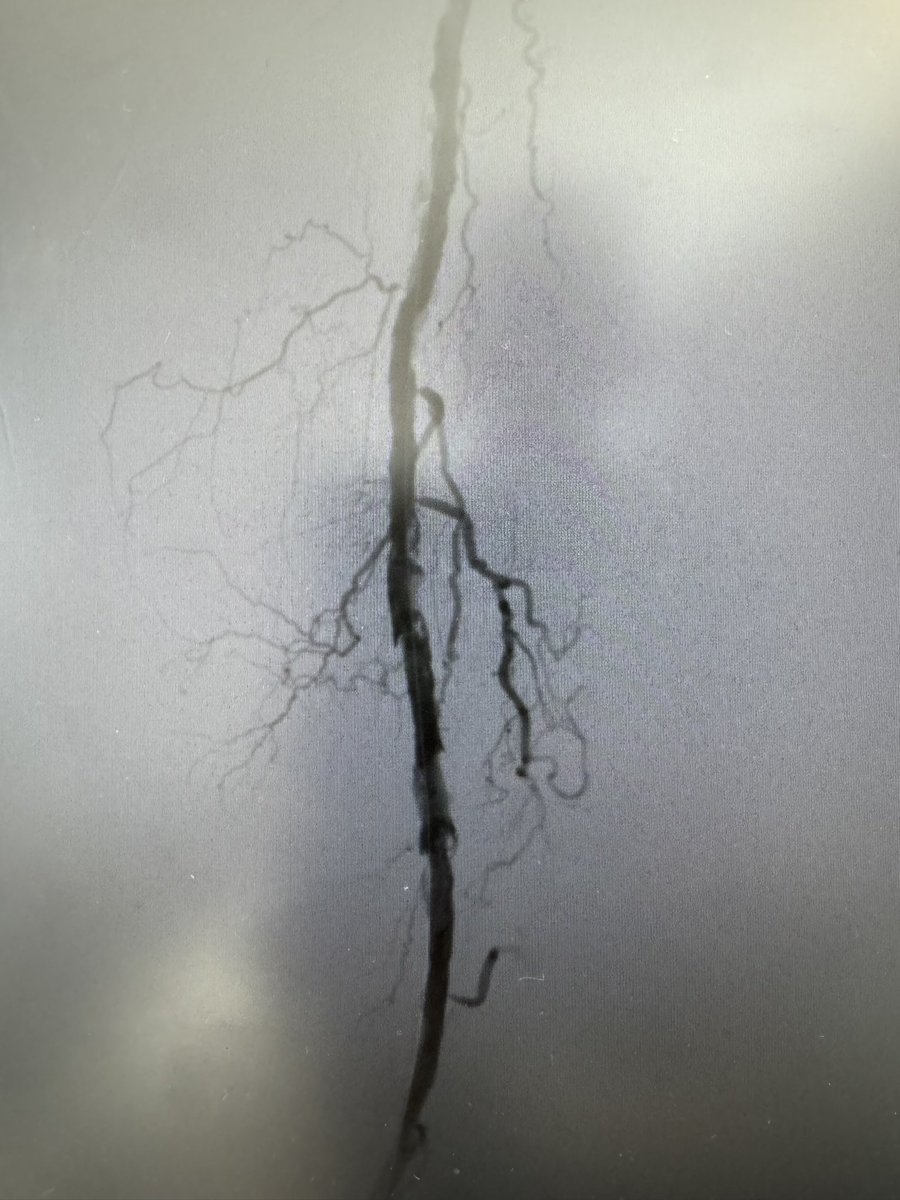

Acute limb femoral pop occlusion tx with 7f bolt Pneumbra . Super impressed .@PenVascular @jcgeorgemd